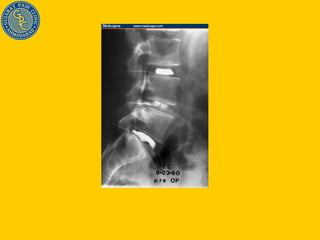

Failed Back surgery syndrome (Post laminectomy pain syndrome) Adhesions – Racz adhesiolysis Recurrent disc herniation at same or adjacent level – treat similarly as disc prolapse Facet joint pain - Denervation Neuropathic pain – LS block / SCS / Intrathecal pump

Failed Back surgery syndrome (Post laminectomy pain syndrome) Adhesions – Racz adhesiolysis Recurrent disc herniation at same or adjacent level – treat similarly as disc prolapse Facet joint pain - Denervation Neuropathic pain – LS block / SCS / Intrathecal morphine pump Intractable pain – SCS / Intrathecal morphine pump